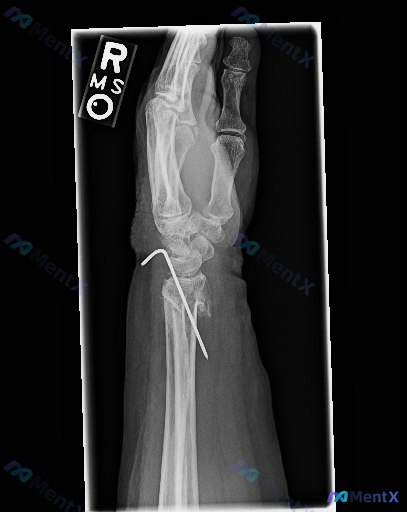

整理到一张右手腕侧位X光片的影像观察资料,分享给大家讨论: 影像基本表现: 1. 骨骼方面:桡骨远端可见粉碎性骨折,断端有移位、成角,骨折线延伸到关节面;有一枚金属克氏针从桡骨远端背侧斜行穿入,经过骨折区,近端弯成钩状,还穿过了部分腕骨(疑似舟骨或月骨区域);腕关节正常解剖对位受影响,掌侧、背侧皮质...